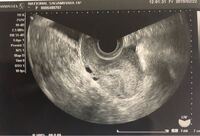

妊娠5週5日で胎嚢が確認されませんでした この黒い部分っぽいけどはっきりと Yahoo 知恵袋

胎嚢確認できました 5週でこれは小さい方ですか Yahoo 知恵袋

本日5週目で産婦人科に行ったところ胎嚢確認できたのですが エコー写真を Yahoo 知恵袋

妊娠5週の胎嚢確認について エコー写真あり 教えていただければ幸いで 妊活 教えて Goo